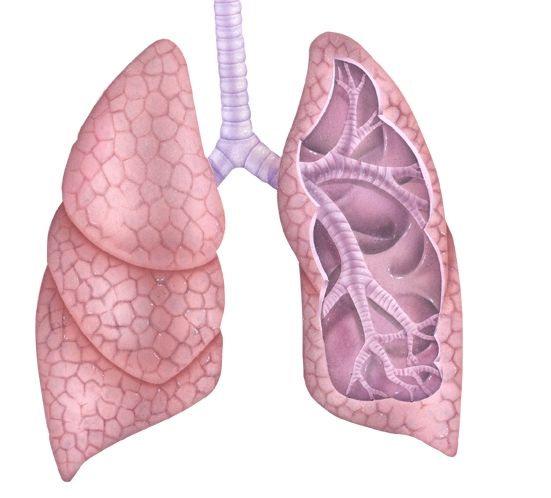

Здоровье дыхательной системы: бронхи и легкие

Раздел: Светлые идеи